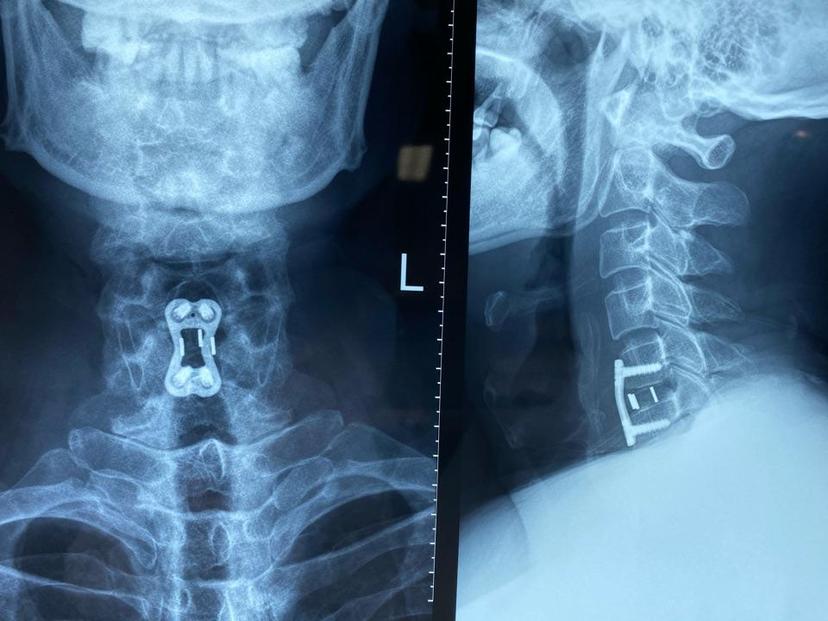

四肢麻木无力,走路不稳,平时需要家人搀扶、拄拐杖走路,行颈前路微创手术,术程不到1小时,切口2cm,术中出血不到10ml,术后第二天下地自行走路,第三天自己弃拐带小跑出院!颈5-6椎间盘突出继发椎管狭窄,脊髓神经严重受压左侧神经严重受压颈椎反弓术中完整取出压迫脊髓神经的椎间盘术后片子位置良好,颈椎反弓完全纠正术后第三天四肢力量明显恢复,麻木感消失,自己甩掉拐杖带小跑出院